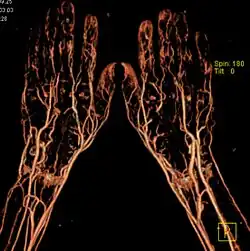

КТ-ангиография

КТ-ангиография позволяет получить послойную серию изображений кровеносных сосудов; на основе полученных данных посредством компьютерной постобработки с 3D-реконструкцией строится трёхмерная модель кровеносной системы.

Спиральная КТ-ангиография — одно из последних достижений рентгеновской компьютерной томографии. Исследование проводится в амбулаторных условиях. В локтевую вену вводится йодсодержащий контрастный препарат в объёме около 100 мл. В момент введения контрастного вещества делают серию сканирований исследуемого участка.